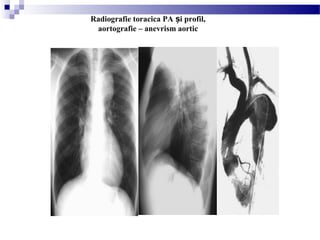

Radiografie toracica PA i profilș

Radiografie toracica PA i profil,ș

aortografie – anevrism aortic